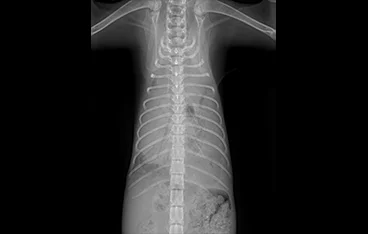

• 횡격막탈장 수술 전

횡격막탈장 수술 후